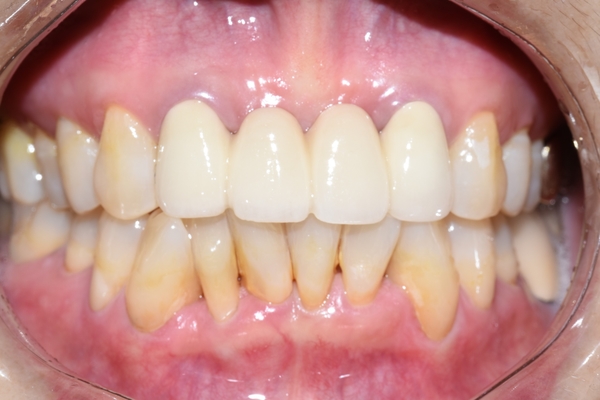

일주일 후 치아 4개짜리 공간에 들어가는 브릿지가 완성되었구요.

환자분이 너무 불투명하게 가짜같은 치아는 싫다고 하셔서

자연광에서, 입 안에서 보일 때 자연스러운 치아로 제작하였습니다.

그리고 당연히 누런 치아보다는 조금 더 밝은 치아가 나으므로 본인 치아와 잘 어우러지면서도

더 밝은 색상으로 디자인하였습니다.

위처럼 입안을 개구기로 훤히 들어냈을 때보다

입술로 그림자도 생기고 살짝 가려진 상태에서 더 자연스러워 집니다.

위 4개 치아가 브릿지 임에도 불구하고 지금 보이는 8개 치아 중

어떤 것이 브릿지인지 티나지 않습니다.

원래도 아름다우셨지만 깨끗하고 깔끔해진 앞니 덕에 더욱더 아름답고 고급스러운 이미지가

되셨습니다.

제작기간: 5일

동일한 위치에서 동일한 조건에서 찍은 사진입니다.

오래되고 깨진 PFM 브릿지 -> 새로운 PFM브릿지로 교체